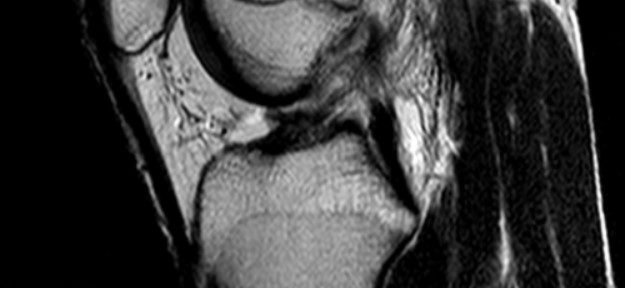

2022年4月4日、患者はサッカーをしている際に右膝をひねり倒れる事故に遭う。その日にMRI撮影が行われた。

- 前十字靭帯(ACL)の完全断裂(中間部の断裂、タイプ2)

- 半月板に損傷の兆候はない。

- 後十字靭帯(PCL)にわずかな損傷がある。

断裂した前十字靭帯は、その連続性を回復したが、その繊維は細いものであった。状態はIhara分類では、gradeIIIに分類される。ラックマンテストでは、膝の不安定性は、3段階中の2と評価された。しかしながら、大腿四頭筋は順調な回復を示していた。これらの混在する結果を踏まえ、保存療法を更に継続することになった。